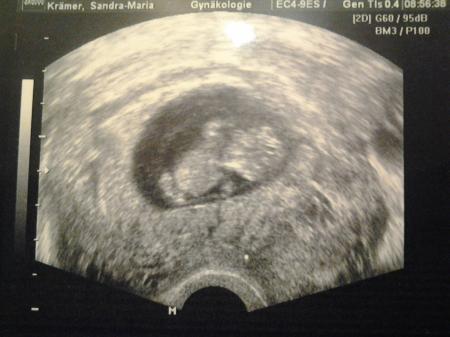

Möchte Euch gerne berichten, dass ich heute endlich nach vier Wochen wieder Ultraschall hatte. Alles dran, was dran sein muss und es ist 4,2 cm groß. Ich war soooo happy! Jetzt muß ich mich bis zum 5.4. gedulden, damit ich es wieder sehen darf... Liebe Grüße Krämerchen

Hier noch das Bildchen